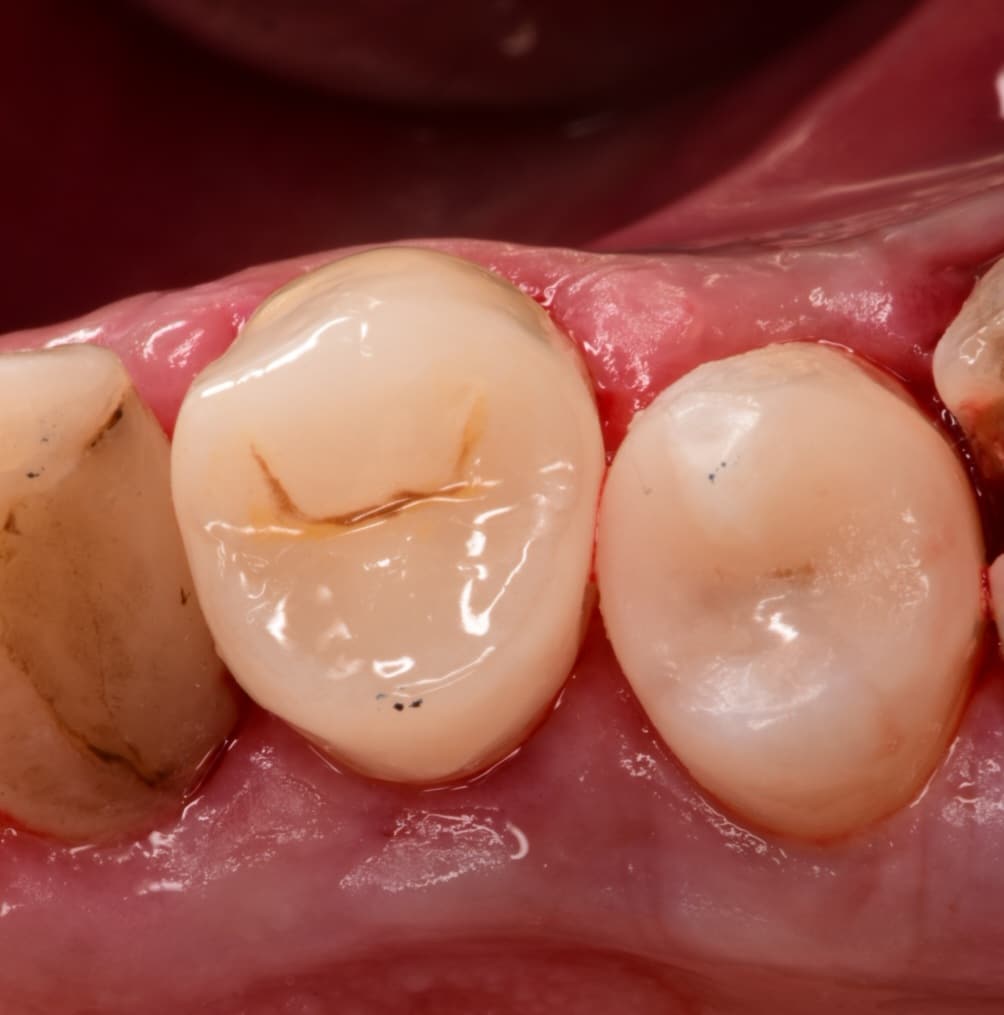

Initial situation as you can see the black upper jaw because of amalgam fillings

Initial situation of upper first premolar bad filling,fracture walls and the esthetic is compromised